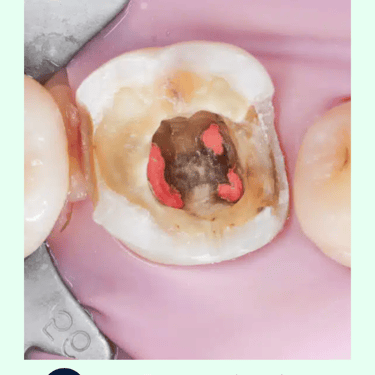

Acceso a la Pulpa: Se hace una apertura en la corona del diente para acceder a la cámara pulpar.

Limpieza y Desinfección: Se eliminan la pulpa y los tejidos infectados del conducto radicular utilizando limas endodónticas. El conducto se limpia y desinfecta con soluciones antimicrobianas.